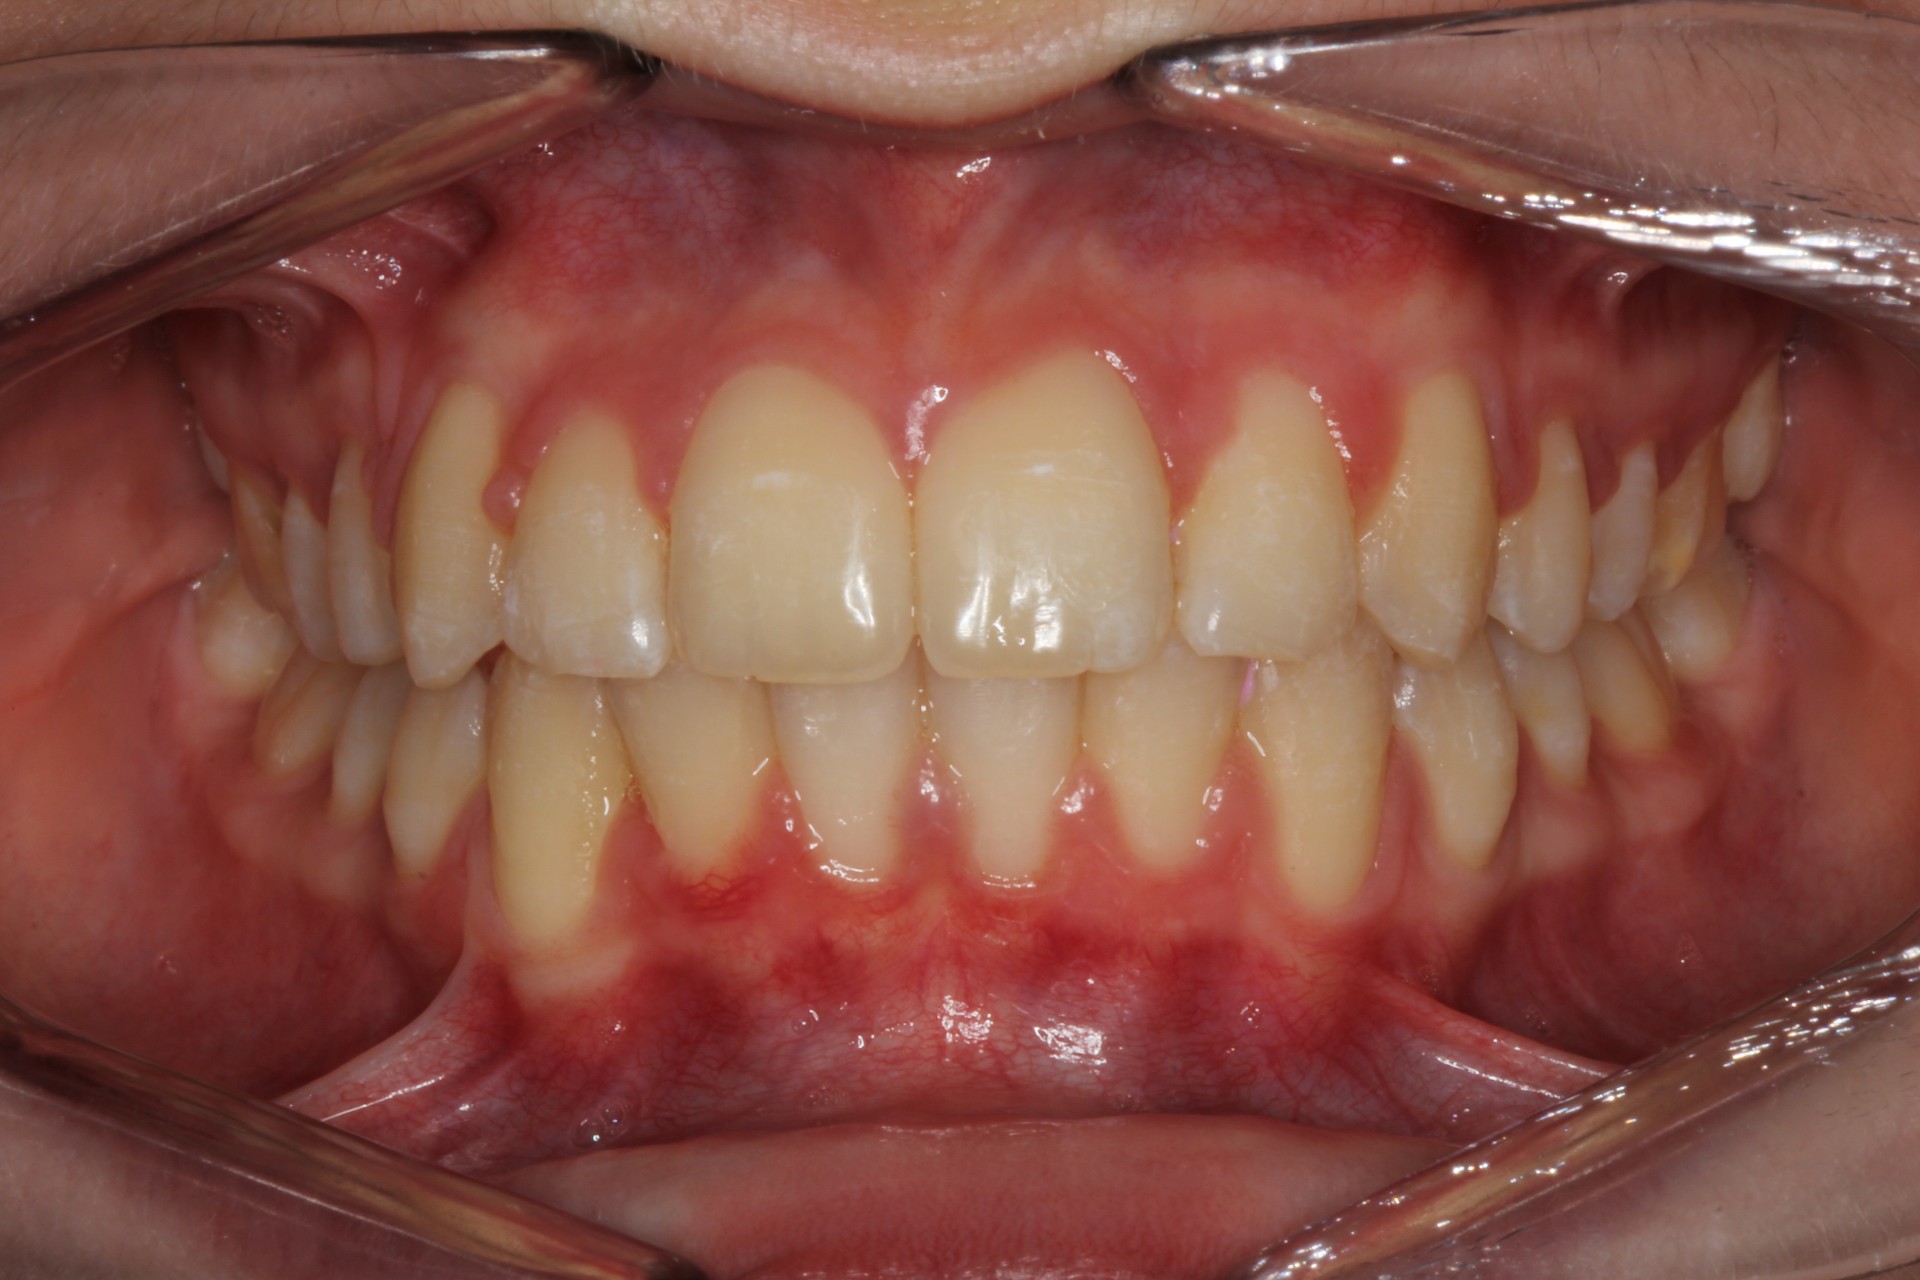

Protruding front teeth – Child case